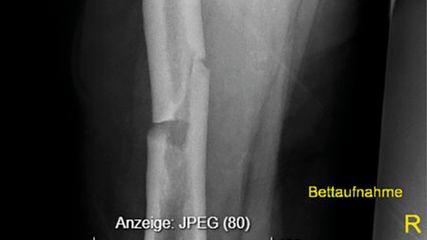

Was die Hüft- und Kniearthrose anlangt, ist der Gelenkersatz mittels Endoprothetik eine Erfolgsgeschichte mit steigender Tendenz. Laut letztem Bericht des Bundesministeriums für Arbeit, Soziales, Gesundheit und Konsumentenschutz (BASG) und der Österreichischen Gesellschaft für Orthopädie (ÖGO) wurden in Österreich z.B. im Jahr 2018 36000 endoprothetische Eingriffe und ca. 4000 Prothesenwechsel durchgeführt.13 Die sorgfältige Rehabilitation und Remobilisierung nach einem endoprothetischen Eingriff trägt zum langfristigen Therapieerfolg bei, wofür spezialisierte interdisziplinäre Einheiten wie Abteilungen für Akutgeriatrie und Remobilisierung (AG/R) optimal geeignet sind.